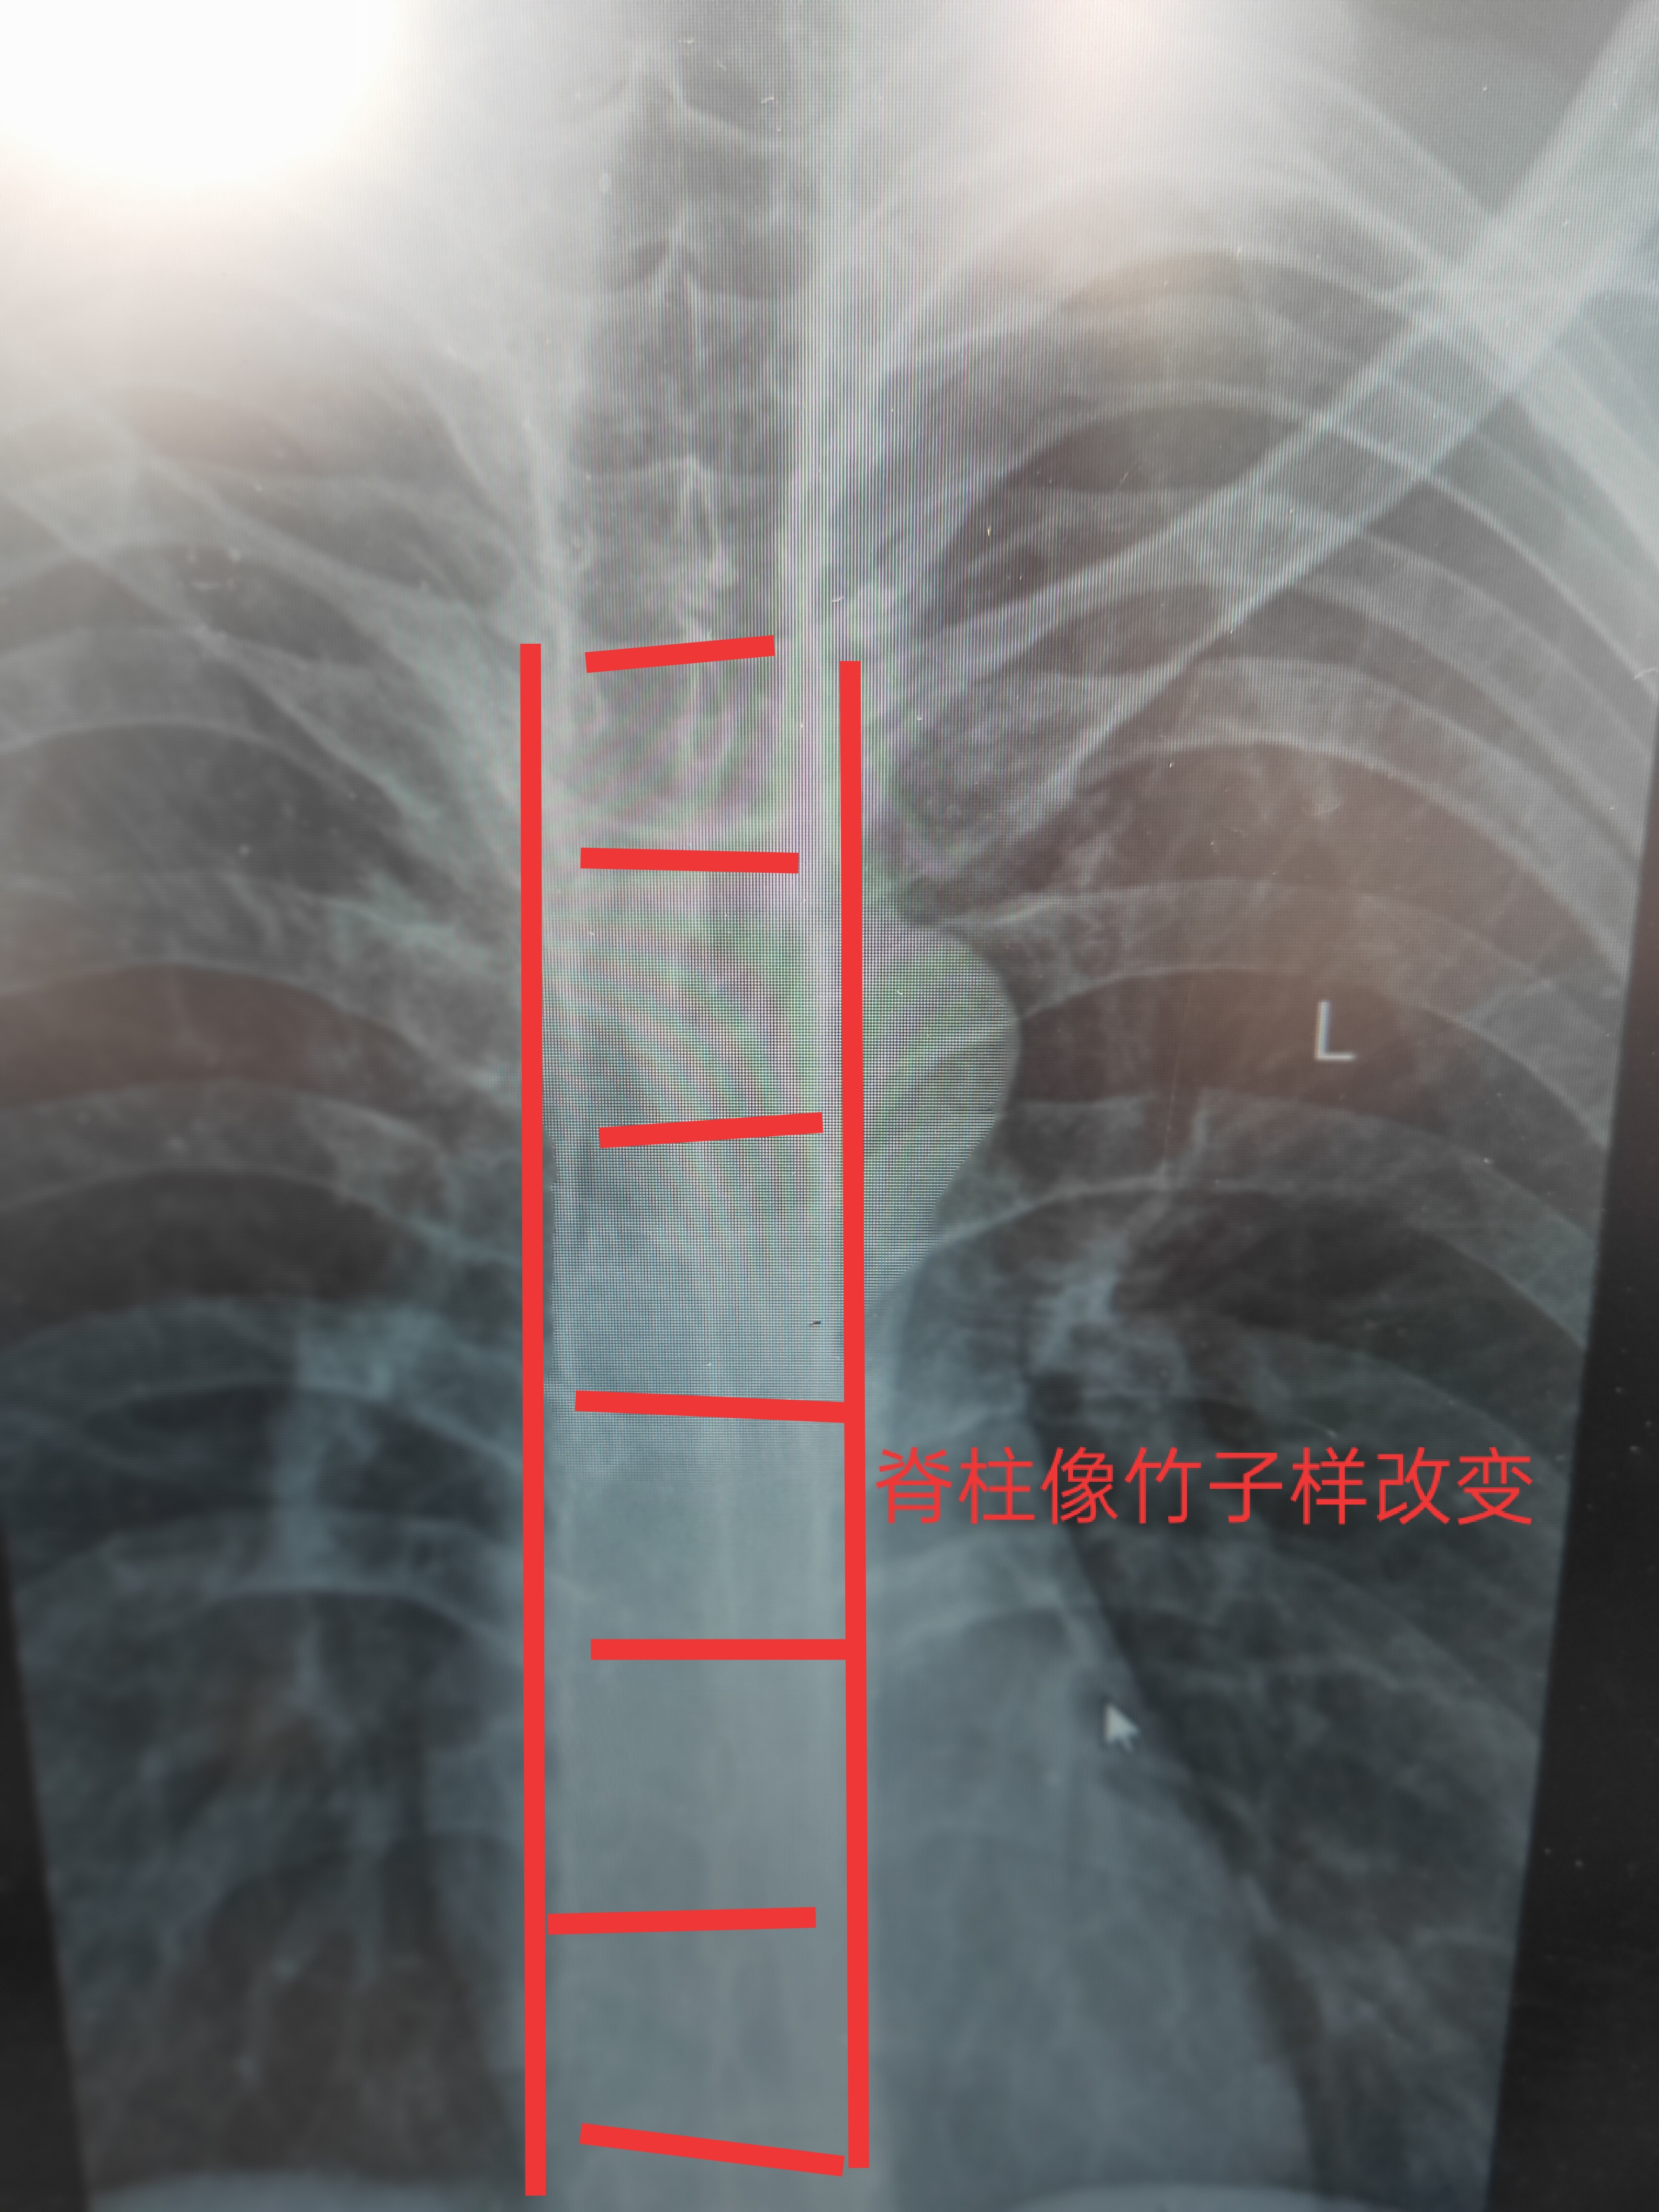

强直性脊柱炎胸椎呈现竹节样改变

X线是基本,主要表现为骶髂关节病变,髂骨处骨质硬化,关节边缘模糊不清,随后关节边缘不整齐,硬化,关节间隙消失,其他变化 有椎体出现骨质疏松 椎间小关节骨质模糊 椎间盘变窄纤维环钙化,前纵韧带 后纵韧带钙化 形成竹节样脊柱,髋关节逐步强直改变。